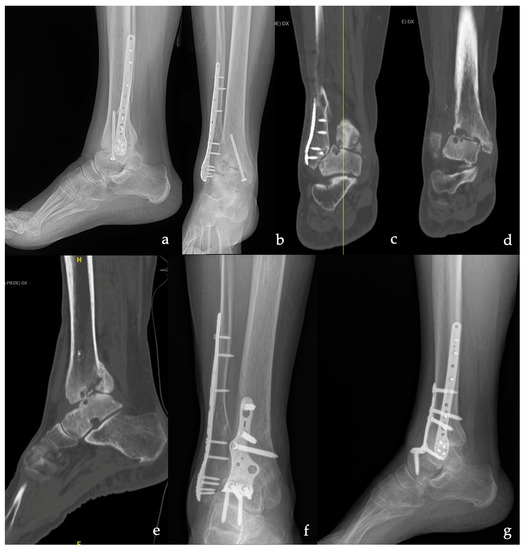

| Type of Plate | Anterior TT | 10 (50%) |

| Anterior TTC | 6 (30%) | |

| Lateral TT | 3 (15%) | |

| Lateral TTC | 1 (5%) | |